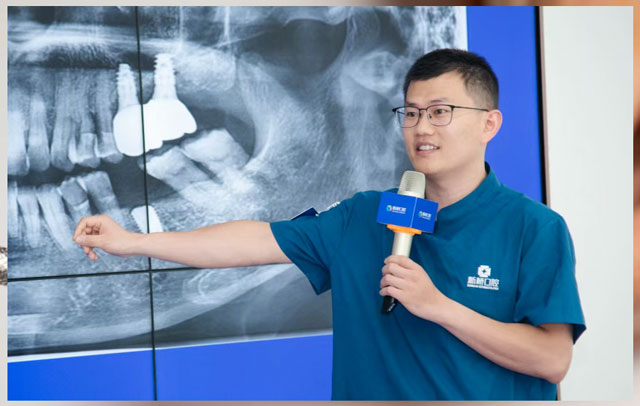

在全球范围内,约30%-60%的人存在智齿异常,包括阻生、错位、萌出不全等。亚洲人因为颌骨相对窄小,阻生智齿的发病率约为60%以上。智齿问题多发生于17-25岁,也就是智齿萌出这个阶段。对于发炎智齿的处理,口腔医生通常会建议拔除。什么样的智齿必须拔?拔智齿真的很可怕吗?今天,我们邀请口腔外科出身,手握上万例智齿拔除手术经验的黄杰医生来为大家详细科普一下。

黄杰 新桥口腔成都总院种植专科主任

四川大学华西口腔医学院口腔外科学硕士

擅长即刻种植、微创种植、半口/全口即刻负重种植;擅长阻生牙、埋伏多生牙的微创拔除,颌骨囊肿的诊治及刮除等。